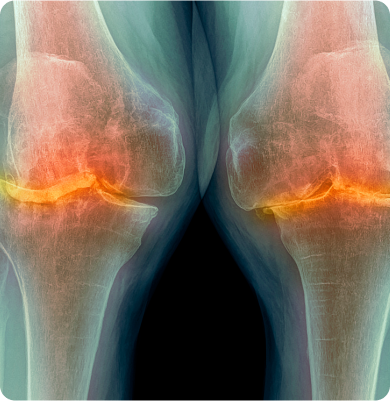

퇴행성관절염

관절을 보호하는 연골이 노화, 반복된 사용 등으로 닳아 없어지며 통증과 염증을 유발하는 질환

주요원인

노화로 인한 연골의 퇴행성 변화가 원인이며 비만, 반복적인 관절 사용, 외상, 유전적 요인 등도 발생에 영향을 줍니다.

주요증상

• 관절을 움직일 때 통증이 발생하며 소리가 나거나 잘 움직여지지 않습니다.

• 관절 부위가 붓거나 열감이 느껴집니다.

• 정도가 심한 경우 관절 변형이나 운동 기능 저하가 나타납니다.